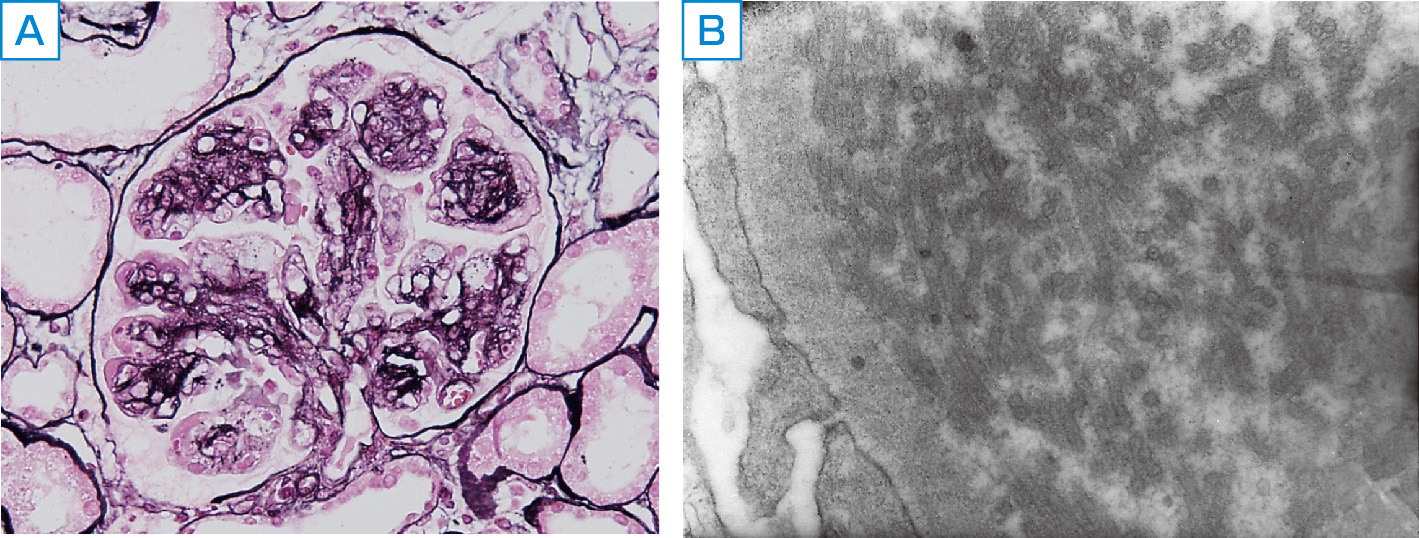

膜性糸球体腎炎 (MGN) は、GN の特殊なタイプです。 MGN は、腎臓構造の炎症により腎臓の機能に問題が生じると発症します。 MGN は、膜外糸球体腎炎、膜性腎症、腎炎などの別名でも知られています。

これらの検査で MGN の存在が示された場合、医師は腎生検を指示することもあります。医師は腎臓組織の少量のサンプルを採取し、分析のために研究室に送ります。この検査の結果は、診断を確定するのに役立ちます。